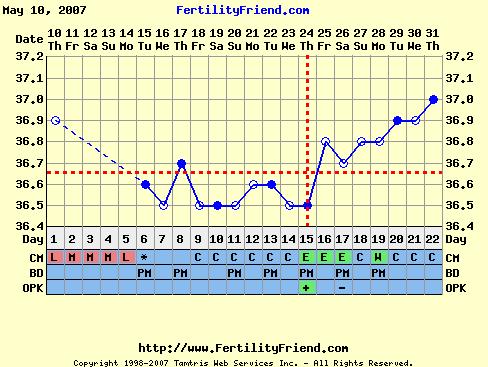

[quote="vedresandi"]P írta:vedresandiöttye:a táblázatok Pandácska keze munkái.Most nincs, de holnap este már lesz.

Babaváró táblába simán be tudsz kerülni,de a babás táblába zebrás teszt a belépő...drukkolok,hogy mihamarabb sikerüljön